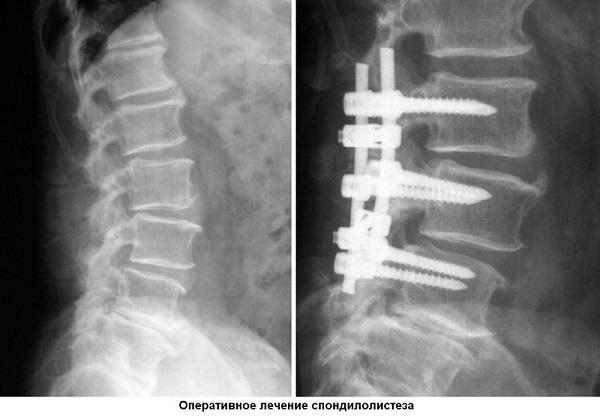

Лечение листезиса можно осуществить двумя основными способами: консервативным (с помощью медикаментов, физиотерапии и лечебной физкультуры) и хирургическим (путем операции). Выбор метода терапии зависит от специалиста, который основывается на результатах диагностики, учитывая стадию заболевания и степень деформации.

Если поражен шейный отдел, в 90% случаев требуется хирургическое вмешательство. Основными показаниями являются усиливающаяся боль и продолжающееся искривление позвоночника, а также отечность околопозвоночных тканей.

Операция (ламинэктомия) помогает восстановить нормальное положение сегментов позвоночника, устранить сдавление нервных корешков и исправить перелом суставной дуги.

Период восстановления после операции занимает около полугода и требует от пациента соблюдения постельного режима, что позволяет костям обрести естественный изгиб.